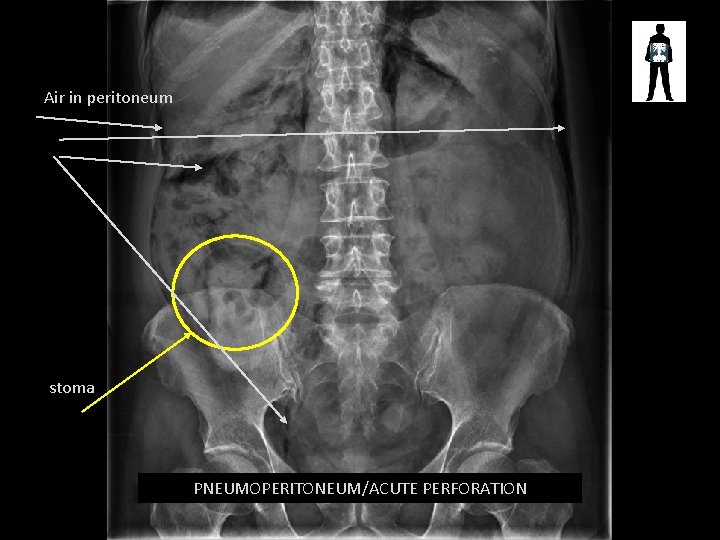

Air in peritoneum stoma PNEUMOPERITONEUM/ACUTE PERFORATION

PERFORATION • Clinical guidelines state – AXR NOT INDICATED FOR PERFORATION – However this patient clearly has a stoma which has been compromised; either during the surgery or following – This would justify the AXR but an erect CXR would have been performed for completeness – Perforation is a SURGICAL EMERGENCY – can cause peritonitis which could be fatal